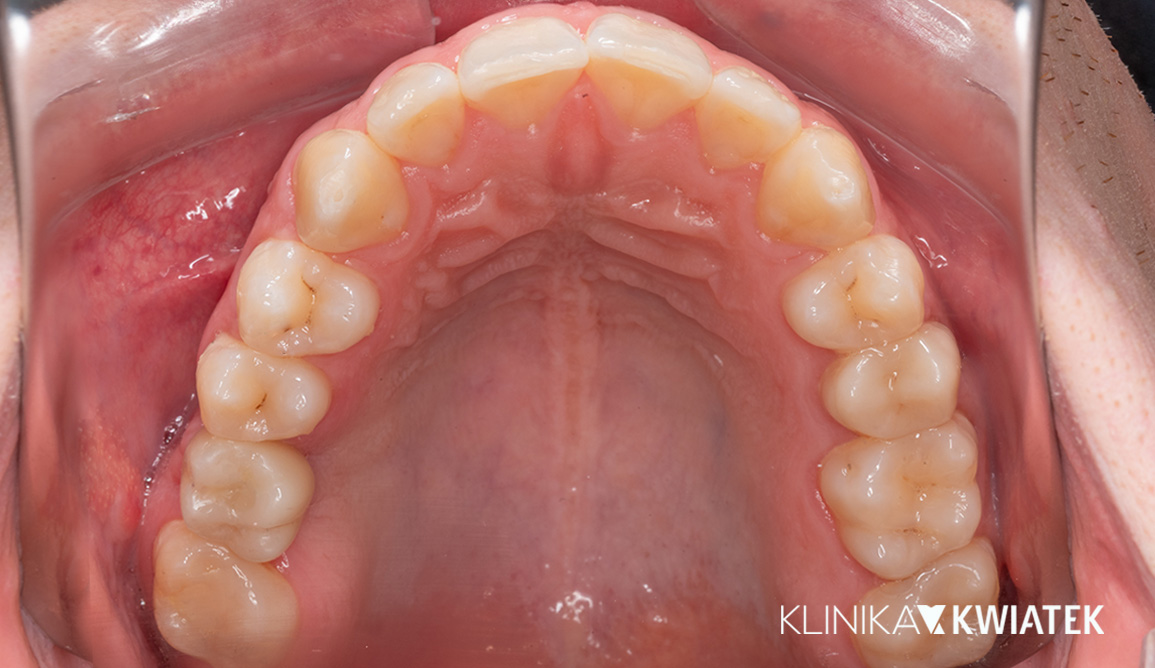

Kompleksowa metamorfoza uśmiechu – od ortodoncji po protetykę i implantologię

Pacjent zgłosił się do kliniki z problemem przetrwałych zębów mlecznych, diastemy i nierównego zgryzu, oczekując szybkiego, ale trwałego efektu estetycznego. Przeprowadzono wieloetapowe leczenie obejmujące higienizację, leczenie zachowawcze, terapię nakładkami ortodontycznymi, implantację oraz nowoczesną protetykę. Finalnym efektem jest harmonijny, biały i zdrowy uśmiech, dopasowany do rysów twarzy.